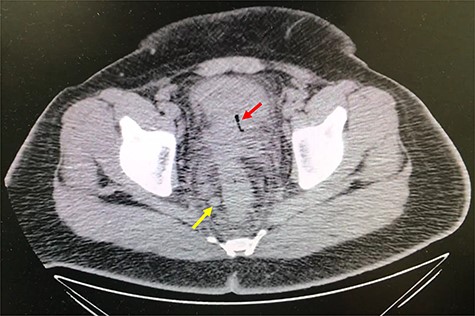

A 32-year-old man with no past medical or surgical history presented to the emergency department (ED) in April 2018, distressed and complaining of worsening pneumaturia for the past 3 days. The patient reported a 2-week history of polyuria, dysuria, suprapubic pain, tenesmus and inability to control his sphincters, prior to the ED-onset presentation. Further history revealed a 50-pound involuntary weight loss in a 5-month period, with partially treated urinary tract infections without resolution. He denied toxic habits, high-risk sexual behavior nor family history for colorectal cancer or inflammatory bowel disease. Based on the symptoms described, the rare triad of Gouverneur’s syndrome related to the EVF was considered. Physical evaluation revealed no palpable anorectal masses, adequate rectal tone and no visible gross blood. Urine analysis showed pyuria, hematuria, proteinuria with urine culture positive for Escherichia coli. Abdominopelvic computed tomography (CT) scan showed circumferential wall thickening of the rectum with surrounding fat stranding and numerous prominent pelvic lymph nodes (Fig. 1). Additionally, the scan showed pericolonic gas and fluid collection with a fistulous tract adjacent to the proximal rectum and the bladder (Fig. 2). In Figure 3, two hepatic hypodense lesions located in the right lobe of the liver were identified suggestive of metastasis. During colonoscopy, at approximately 20 cm from the anal verge a large, firm, irregular, friable, concentric mass was identified obstructing 95% of the lumen (Fig. 4). During surgery, the mass was not amenable for resection, due to its low pelvic location and size; a loop colostomy was performed for decompression, with liver tru-cut needle biopsy. Intraoperative cystoscopy was unsuccessful in placement of ureteral stents due to tumor invasion to the bladder.

Axial abdomen and pelvis CT scan showing fistulous tract adjacent to the proximal rectum and the bladder (red arrow) and enlarged lymph nodes (yellow arrow).